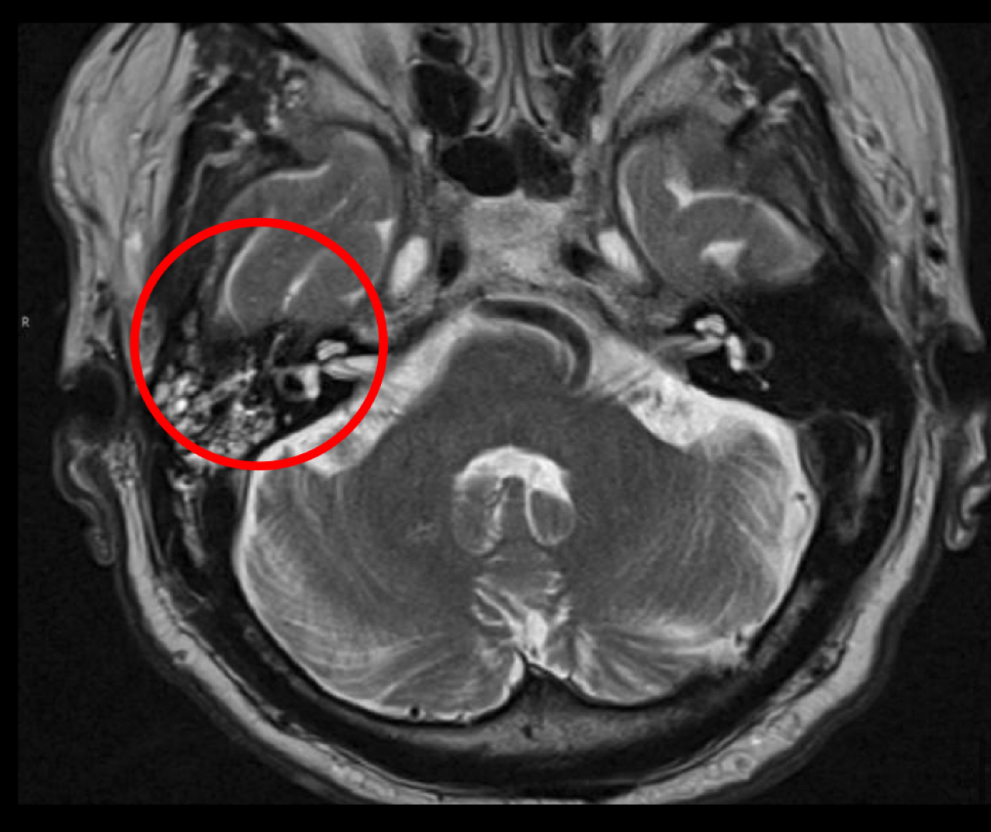

Q

Utilidad rm

A

ver extension intracraneal

en t2 q se ve

hiperseñal

Disminucion de señal en seno signoide

Capta contraste